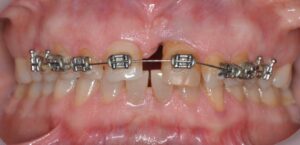

– tratamentul ortodontic: prin acesta dintele modificat se trage în jos prin miscari controlate de aparatul ortodontic iar dintele coborat în acest fel va trage dupa el, pe de o parte osul din profunzime si va creste nivelul și volumul sau, și pe altă parte, marginea gingiei care este nevoie sa ajungă la nivelul dintelui sanatos vecin pentru simetrie.